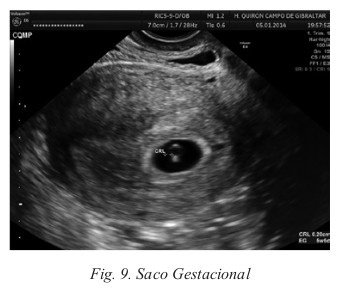

La ecografía transvaginal supone el método de elección para el diagnóstico precoz de la gestación. A partir de las 4 semanas de amenorrea o 18-20 días postfecundación, se puede visualizar la existencia de un saco gestacional de 2 o 3 mm de diámetro. El saco gestacional es una estructura anecoica o sonolucente rodeada por un anillo ecorrefringente que corresponde a la reacción decidual (Fig. 9).